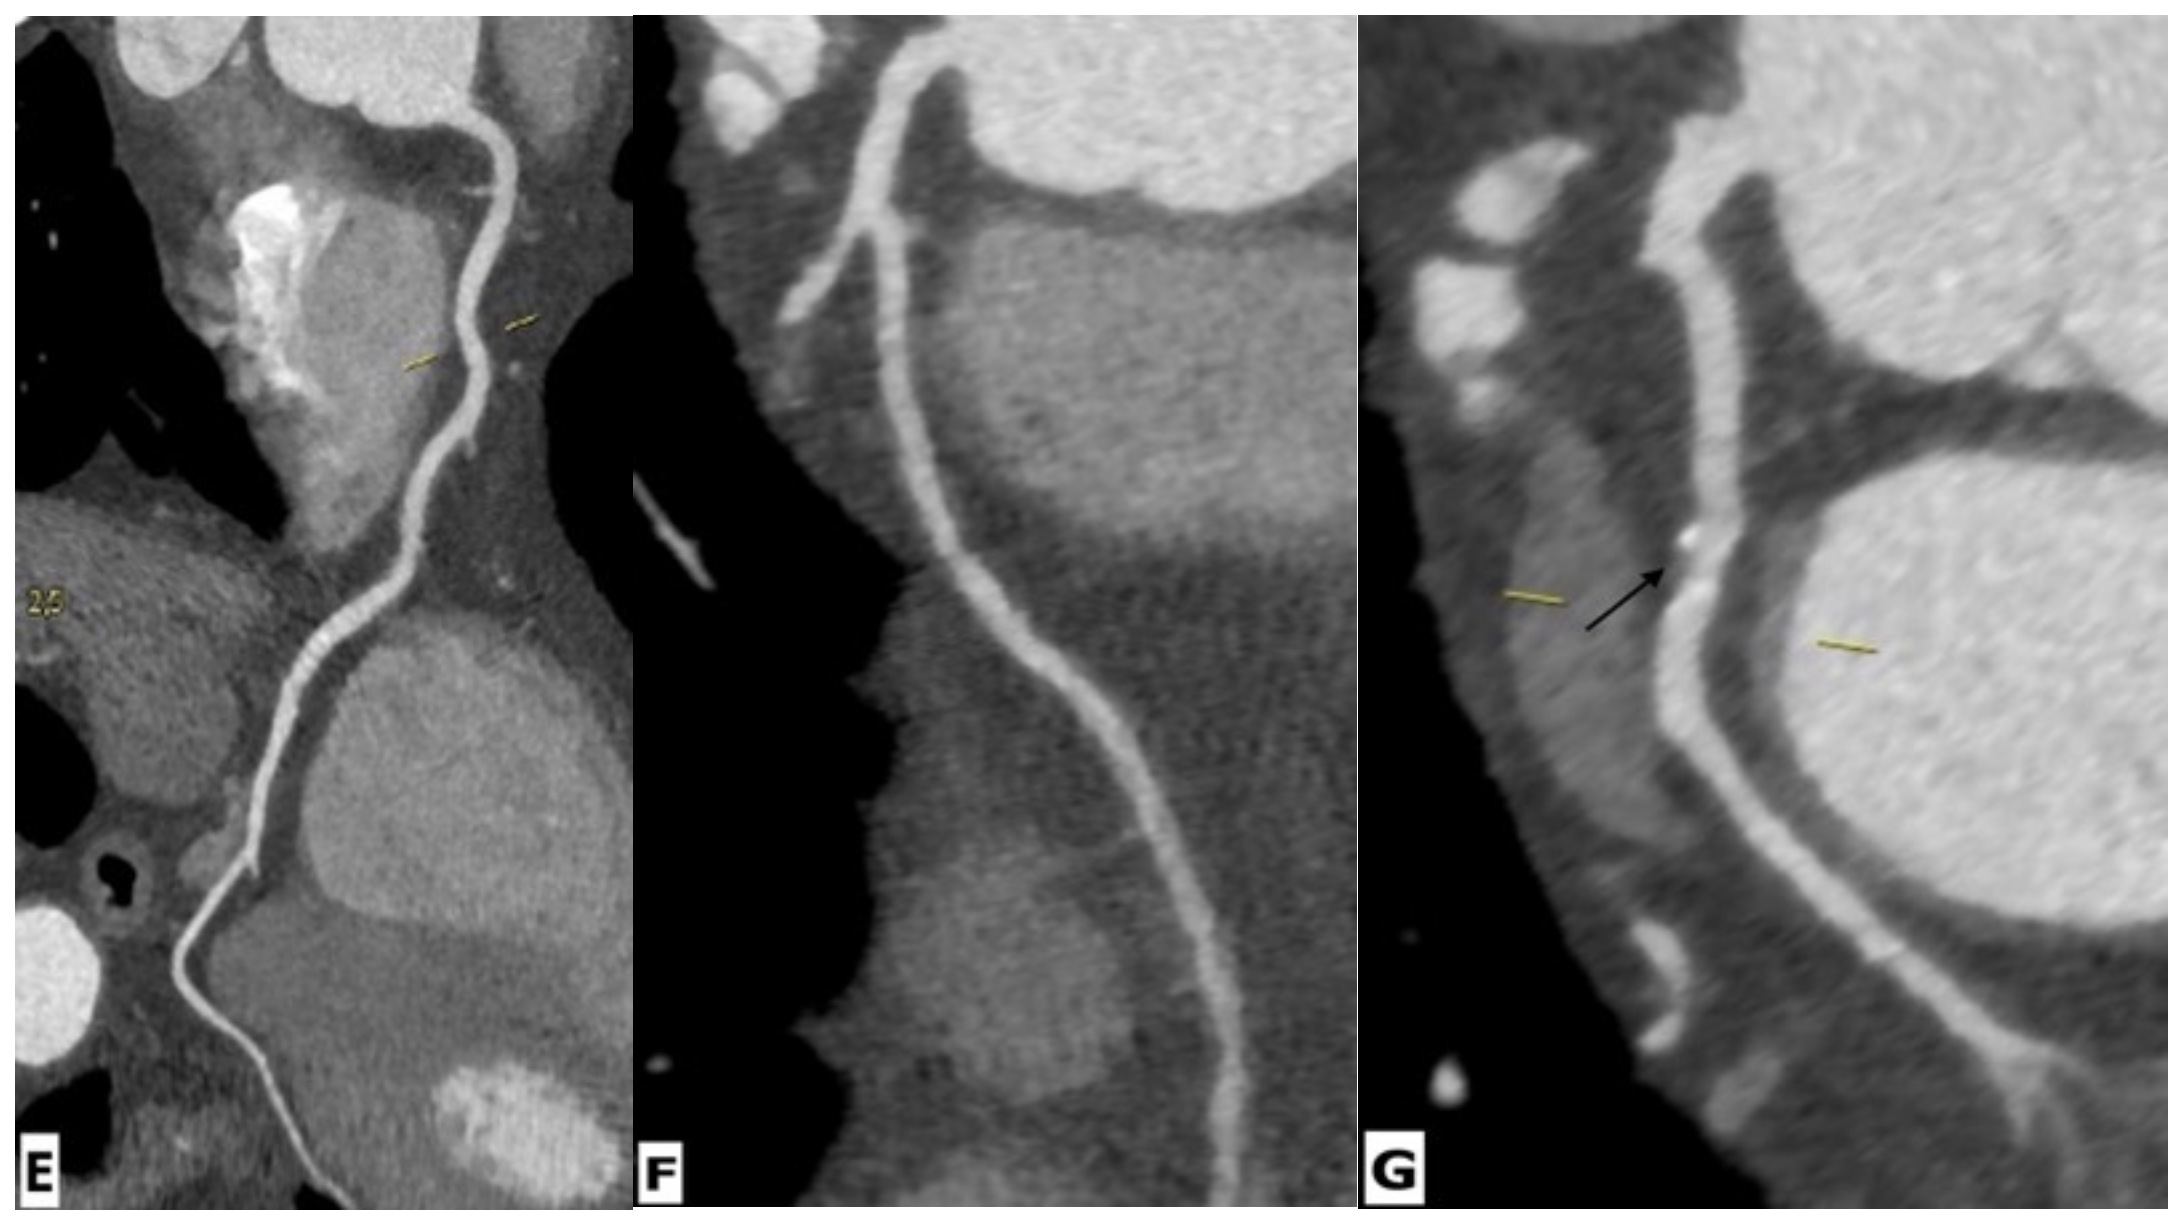

Figure 5.

Cardiac magnetic resonance imaging in a 65-year-old HIV-infected male patient with microvascular coronary dysfunction. (A) Mid-ventricular short-axis late gadolinium enhancement image showing no ischemic pattern. Stress CMR was performed via regadenoson administration. (B–D) Stress protocols images of three ventricular slices (basal, mid-ventricular, and apical slices) show diffuse subendocardial hypoperfusion (arrows) due to microvascular dysfunction. (E–G) Multiplanar reformatted contrast-enhanced computed tomography images showing the right coronary artery (RCA), left anterior descending artery (LAD), and left circumflex artery (LCx), respectively. RCA and LAD are normal without any atherosclerotic diseases. LCx shows focal mixed plaque causing minimal luminal stenosis (arrow).